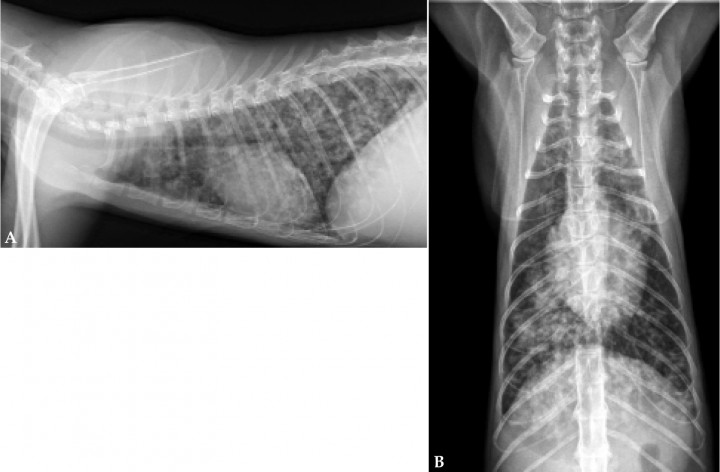

Se presenta en consulta un gato macho, Común Europeo de 3 kg, adulto, procedente de una protectora de animales, con un cuadro de disnea, tos y crepitaciones bilaterales a la auscultación pulmonar. El hemograma evidenció leucocitosis con neutrofilia y la bioquímica no mostró hallazgos significativos. El grado leve de disnea permitió la manipulación del paciente y la realización de radiografías torácicas en las proyecciones lateral derecha y ventrodorsal (Figs. 1A y 1B).

<p>Radiografías de tórax de un gato Común Europeo. (<strong>A</strong>) Proyección lateral derecha. (<strong>B</strong>) Proyección ventrodorsal.</p>

Radiografías de tórax de un gato Común Europeo. (A) Proyección lateral derecha. (B) Proyección ventrodorsal.

Las radiografías muestran un patrón difuso, broncointersticial estructurado (miliar a nodular), con reactividad peribronquial en todos los campos pulmonares y opacidad alveolar leve en los campos pulmonares caudodorsales. El patrón pulmonar impide la visualización del borde de la vasculatura lobular caudal de los grandes vasos y, en menor grado, del borde caudal de la silueta cardíaca, especialmente en la proyección lateral. El resto de estructuras intra y extratorácicas no presentan anormalidades.

Los hallazgos radiográficos no son necesariamente patognomónicos, pero la evidencia de enfermedad broncointersticial pulmonar a menudo es evidente (Figs. 1A y 1B).

Los hallazgos radiográficos varían según la carga parasitaria y el tiempo de inicio de la infección desde un patrón pulmonar broncointersticial multifocal nodular leve, a menudo en los lóbulos pulmonares caudales, hasta un infiltrado alveolar difuso.[ Hawley MM, Johnson LR, Traversa, D, et al.: Respiratory distress associated with lungworm infection in a kitten. J Feline Med Surg. Open Reports 2016; 1-6. ]